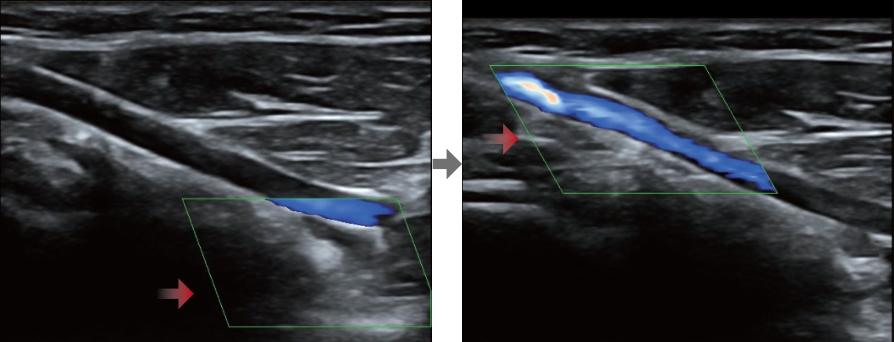

'Full HD'? ?? ?? 1? ?? ???? ?? ???? ???? ??? ????? ?? ???? ??????. ??? ????? ??? ???? ???? ?? ??? ???, ??? ???, ??? ? ?? ???? ??? ??? ???.

'Full HD' ?????? ? ?? ???? Full HD? ?? DC-40? ???? ??? ??? ???? ??? ? ?? ?????. 'Full HD'? ??? ??? ????? ? ?? ?? ???, ? ?? ????? ??, ??? ? ?? ? ?? ??? ? ??? ??? ?????.

Full HD ??? ?? DC-40? ???? ????? ???? ??? ?? ???? ??? ?? ?? ??? ???? ??? ?? ???? ??? ?? ??? ?????.